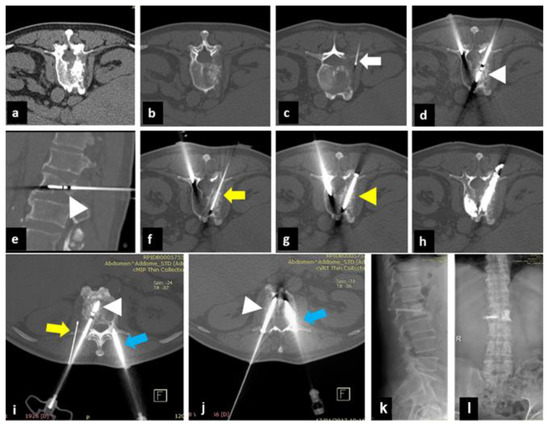

2.1. Treatment Technique